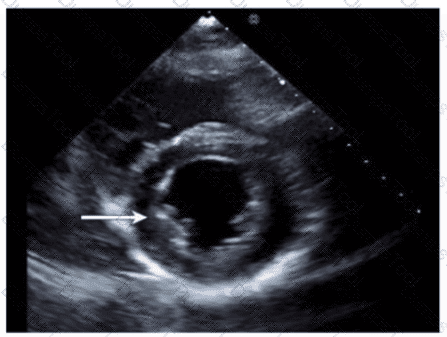

Which congenital abnormality is most consistent with the findings in this video?

Which step is next in further evaluation of the abnormality shown in this video?